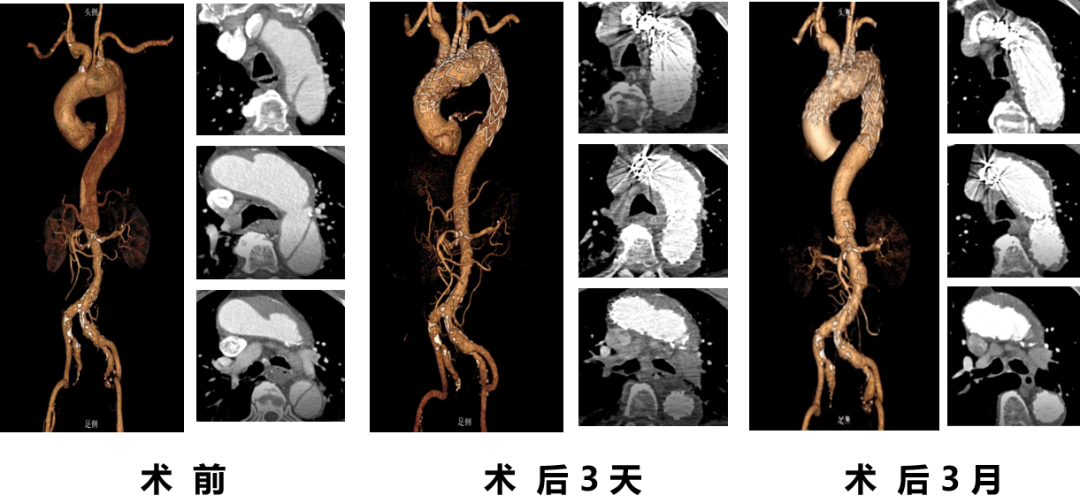

★ 病例3

顾某,男,50岁,“胸背部疼痛3天”入院,主动脉CTA提示:主动脉夹层(多发性主动脉弓部溃疡);2.降主动脉假性动脉瘤;3.主动脉壁内血肿(B型)。

术前CTA

术前造影

术后造影

手术用时140分钟